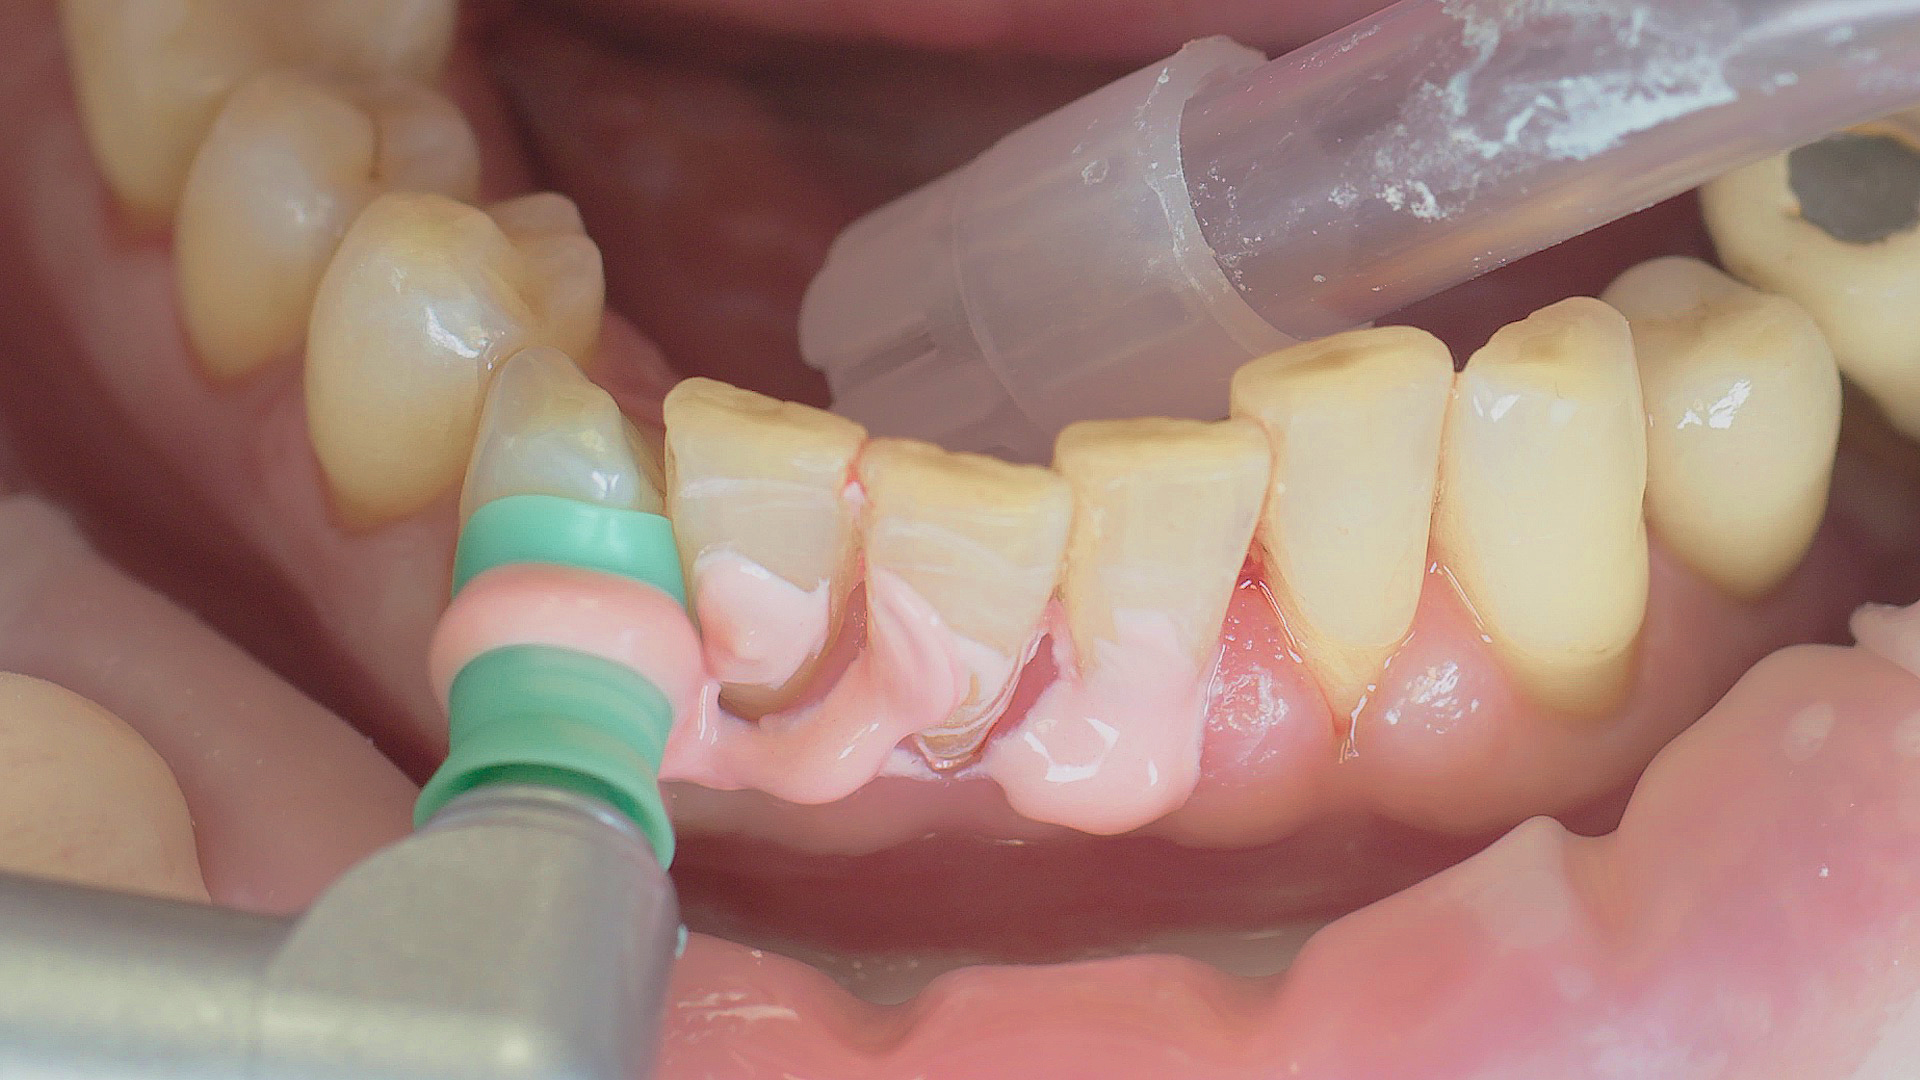

Removal of subgingival coatings (debridement) is carried out using sonic or ultrasonic devices and special periodontal tips as initial periodontal treatment (Fig. 3). Manual instruments can also be used. Further surgical and/or regenerative measures may be necessary, depending on the situation.

In the periodontal aftercare subsequent to implantation, soft (biofilm) and hard coatings are regularly professionally and mechanically removed.[16, 17] In the subgingival and supragingival areas, ultrasonic devices are generally used for this (Fig. 4), in combination with manual instruments where necessary. Alternatively, subgingival air polishing can be used in combination with periodontal attachments and powders.[18]